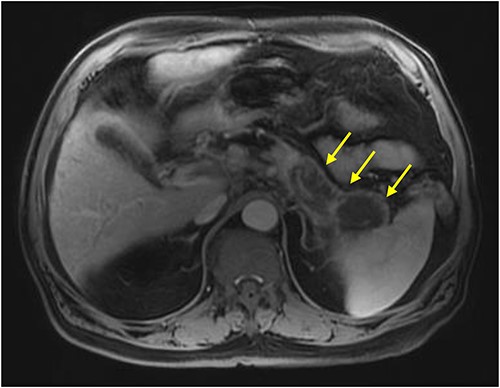

Initial imaging with computed tomography (CT) of the chest, abdomen, and pelvis with IV contrast identified a hypoenhancing infiltrative pancreatic tail mass with central necrosis, as seen in Fig. 1. Given the diffuse hypodensity and without evidence of metastatic disease, findings were favored to represent pancreatitis with pancreatic necrosis. Magnetic resonance cholangiopancreatography (MRCP) was subsequently obtained which again revealed findings favored to be pancreatic necrosis rather than malignancy, as seen in Fig. 2. He then underwent an endoscopic retrograde cholangiopancreatography, which found a common bile duct stone which was extracted, as well as a high-grade benign-appearing ampullary stenosis, which was brushed and stented. The patient’s hyperbilirubinemia unfortunately failed to resolve following biliary ductal decompression. His highest documented total bilirubin was 24 mg/dl, largely from a direct component. Finally, he underwent an endoscopic ultrasound (EUS), which identified a mass in the body and tail of the pancreas advancing into the second portion of the duodenum with extensive surrounding ascites. Two fine-needle biopsies were taken, which resulted positive for invasive adenocarcinoma.

MRI abdomen (MRCP) with IV contrast: axial image showing diffuse enlarged hypointense signal of pancreatic body and tail on T1 weighted imaging encircled by a thin rim of enhancement representing normal pancreatic tissue (arrows).